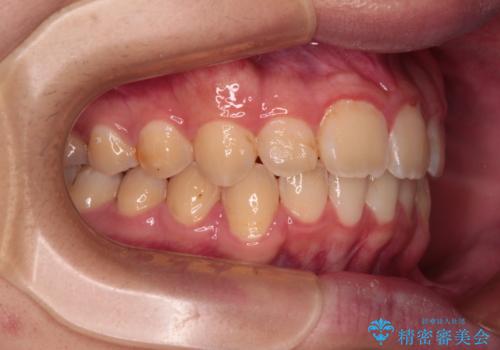

- 深く咬みこんだ前歯と、それに伴い前方に突出した上顎前歯を気にして来院された患者様です。

下顎の歯列は、奥歯が前方に傾斜し、前歯が上顎の歯の付け根に食い込むように内側に傾斜していました。

また、左右の犬歯の位置関係は上顎歯列が前方に位置する咬み合わせとなっており、インビザライン単体で治療するよりは、ワイヤー装置や補助装置を併用した方がより良い仕上がりになることが期待されました。

来院時は学生であったので、補助装置により上顎臼歯を後方に移動させ、下顎歯列はワイヤー装置による傾斜を改善させ、就職のタイミングでインビザラインにて仕上げていくこととしました。